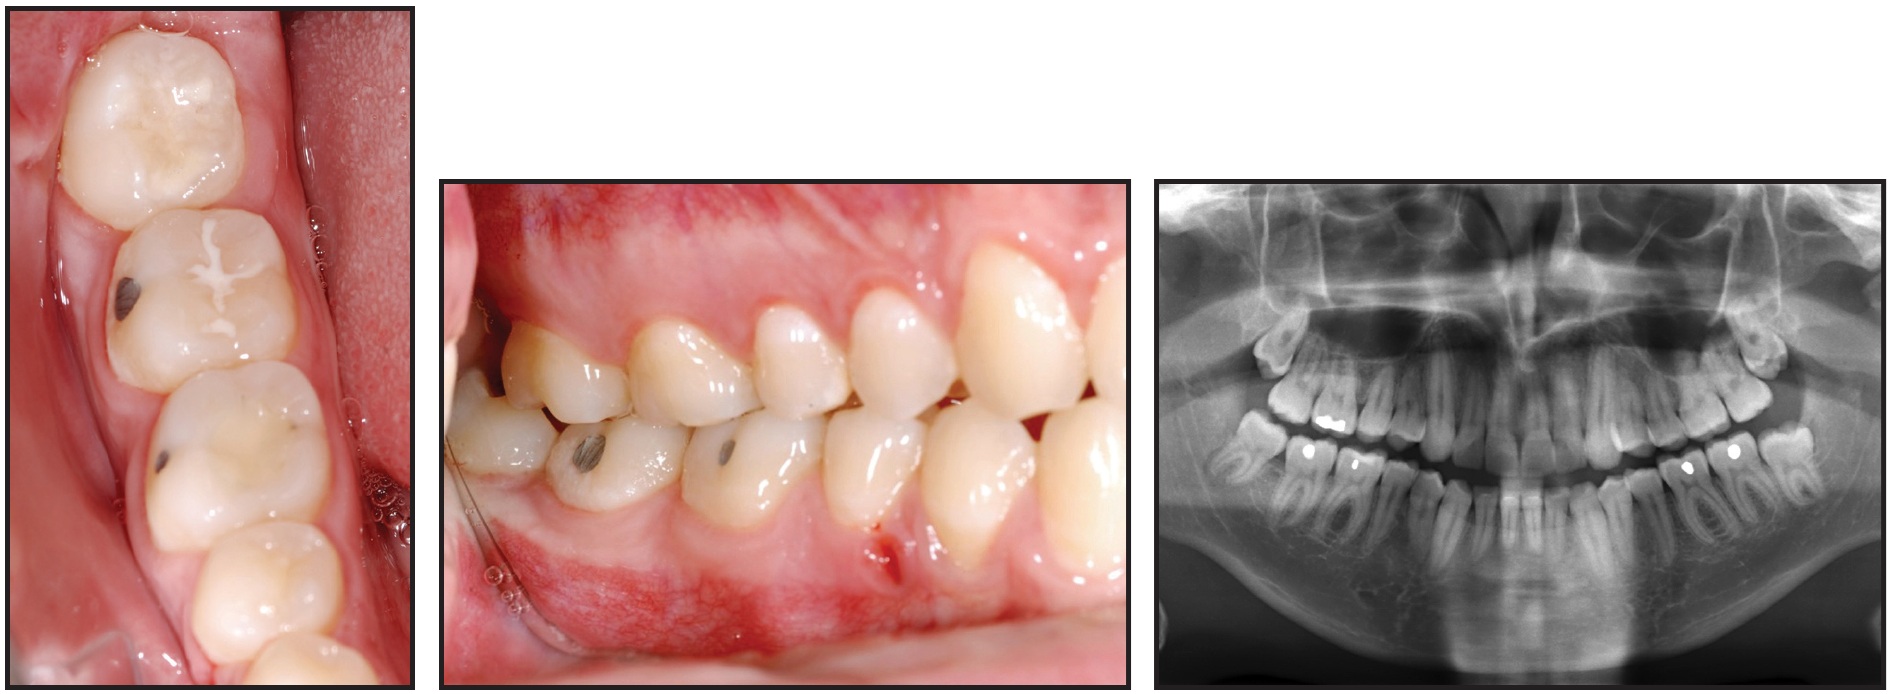

This 22-year-old male had completed comprehensive orthodontic treatment two years earlier (Fig. 3).

Fig. 3 Case 1. 22-year-old male patient with mesially impacted lower right third molar two years after completion of previous orthodontic treatment.

A panoramic x-ray showed that all third molars were present, with the lower right one mesially impacted. A mini-implant was inserted between the roots of the lower right premolars, and, after minimal exposure of the distal cusps, a tube was bonded. The uprighting mechanics described above were applied, delivering a counterclockwise moment to the third molar (Fig. 4).